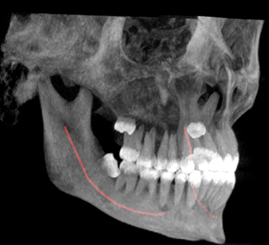

Estudios de imagen

Como estudio imagenológico inicial, se le realizó ortopantomografía, donde se apreció la lesión radiopaca de bordes irregulares y difusos en el cuadrante superior derecho que se extendió en sentido cefálico caudal con ocupación del seno maxilar derecho, y en sentido mesio-distal desde la unidad 1.3 hasta la unidad 1.7. Posteriormente se le indicó una tomografía computarizada cone beam, donde se apreció que el límite superior de la lesión coincide con el borde inferior del cuerpo malar, extendiéndose hasta el pilar cigomático maxilar, tal como se muestra en las Figuras 3, 4 y 5.

Figura 3. Reconstrucción 3D en una vista trans axial de los huesos del macizo cráneo facial y la zona afectada por la lesión. Fuente: Historia Clínica Postgrado Cirugía bucal ULAC-IDOLA Julio 2021

Figura 4. Reconstrucción 3D volumen rendering, en una vista frontal de los huesos de la cara y zona afectada por la lesión. Fuente: Historia Clínica Postgrado Cirugía bucal ULAC-IDOLA Julio 2021

Figura 5. Reconstrucción multiplanar donde se observa la displasia en cortes: axial, sagital y coronal. Fuente: Historia Clínica Postgrado Cirugía bucal ULAC-IDOLA Julio 2021